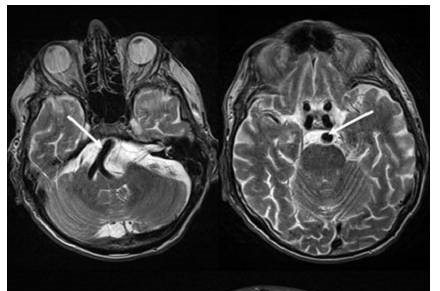

高血压患者出现脑干高密度影,要首先除外高血压引发脑出血。我们立即对患者进行头颈血管核磁检查,以明确脑部血管病变。头颈血管核磁却提示,脑干部的高密度影并不是脑出血,而是椎基底动脉扩张,压迫脑干。

请神经科会诊,诊断为:椎基底动脉延长扩张综合征(VBD)。

(所椎基底动脉延长扩张综合征是一种少见且病因不清的椎基底动脉壁受累的疾病,动脉延长扩张继发邻近脑组织受压,部分患者由于脑干压迫,会神经发射性出现高血压。该病起病隐匿,并且研究相对较少,很容易漏诊。)